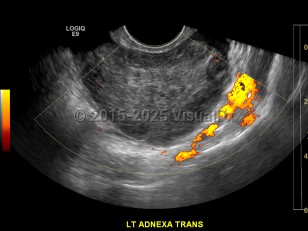

Imaging Studies image of Ovarian torsion - imageId=7904892. Click to open in gallery.  caption: '<span>Ultrasound image demonstrates  enlarged, heterogeneous left ovary with peripheralized follicles and  absence of flow. Findings consistent with clinical diagnosis of ovarian  torsion.</span>'

Ultrasound image demonstrates enlarged, heterogeneous left ovary with peripheralized follicles and absence of flow. Findings consistent with clinical diagnosis of ovarian torsion.